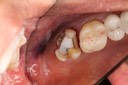

Kyle Chock#14 pre-op

Kyle Chock #14 caries removal

Kyle Chock #14 prep